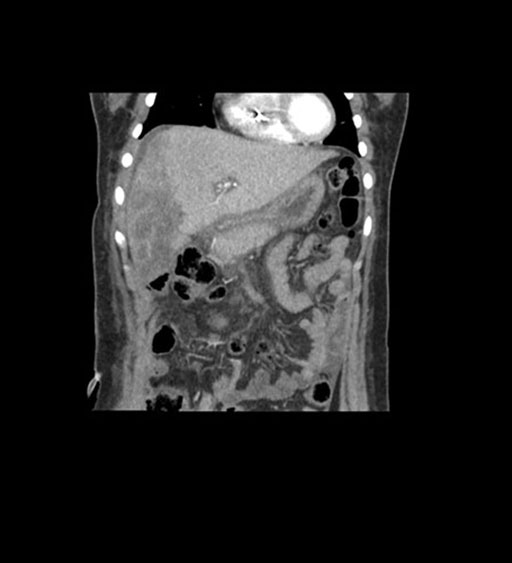

Coronal Venous